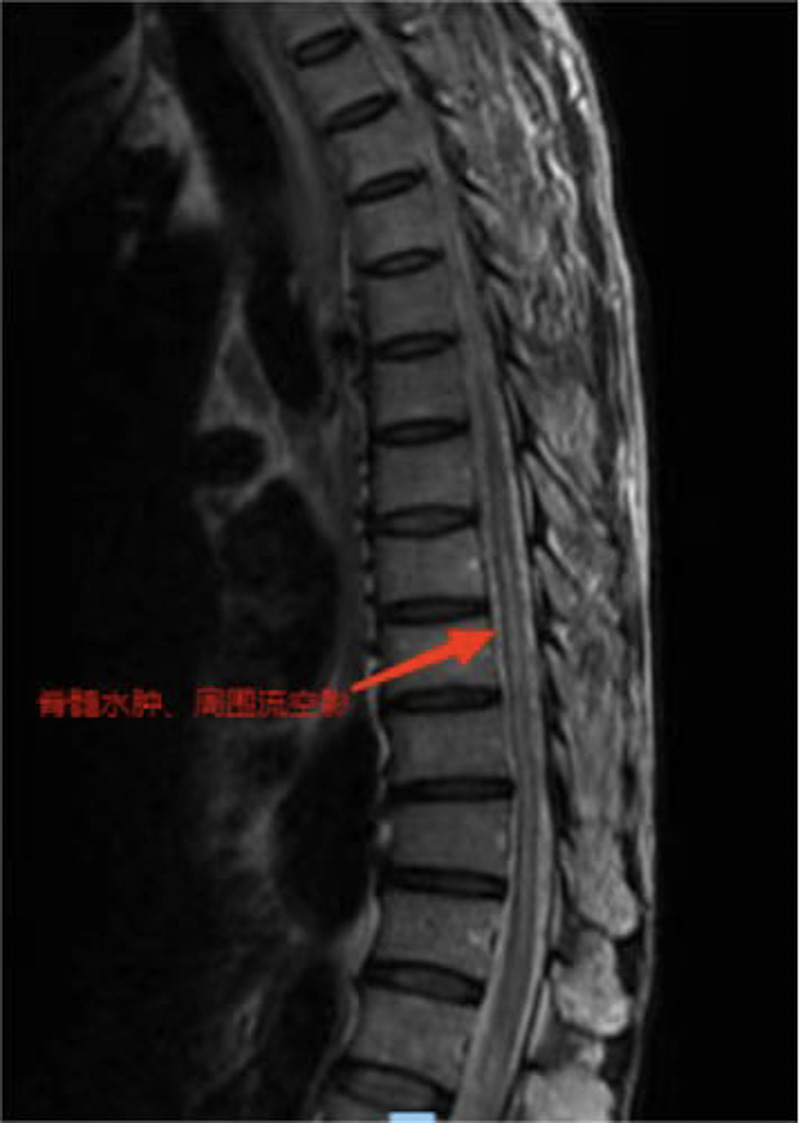

方先生(化名)年過(guò)六旬,身體硬朗,但是近一年來(lái)逐漸出現(xiàn)了下肢乏力,一開(kāi)始只是不愿多走路,半年前,乏力癥狀已經(jīng)影響到了正常生活,這才引起了他的重視。此前雖然方先生輾轉(zhuǎn)就醫(yī),卻始終無(wú)法得到明確的診斷,抱著最后一線希望,他于日前來(lái)到了柳州市人民醫(yī)院神經(jīng)外科就診。醫(yī)生很快在患者磁共振檢查結(jié)果中找到了關(guān)鍵線索——方先生脊髓血管有異常,考慮下肢乏力與此有關(guān)。經(jīng)過(guò)詳細(xì)的檢查和分析,神經(jīng)外科團(tuán)隊(duì)診斷方先生患的是胸椎硬脊膜動(dòng)靜脈瘺。

救治刻不容緩,醫(yī)院立即組織神經(jīng)外科、神經(jīng)內(nèi)科及麻醉科等開(kāi)展多學(xué)科會(huì)診,結(jié)合方先生的情況綜合判斷,為他設(shè)計(jì)了治療方案,經(jīng)胸髓CTA、血管造影,明確瘺口在胸10椎體水平,決定實(shí)施顯微鏡小切口半椎板入路手術(shù)切除瘺口。

術(shù)后經(jīng)過(guò)醫(yī)護(hù)團(tuán)隊(duì)細(xì)心的治療護(hù)理,復(fù)查磁共振胸髓水腫消失,患者雙下肢感覺(jué)及乏力癥狀明顯改善。